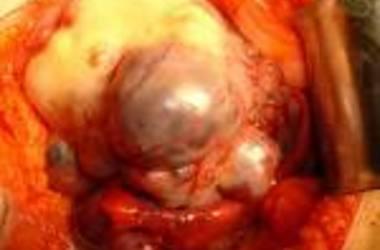

Ovarian cancer is a type of cancer that begins in the ovaries. Women have two ovaries, one on each side of the uterus. The ovaries — each about the size of an almond — produce eggs (ova) as well as the hormones estrogen and progesterone.

Ovarian cancer often goes undetected until it has spread within the pelvis and abdomen. At this late stage, ovarian cancer is more difficult to treat and is frequently fatal. Early-stage ovarian cancer, in which the disease is confined to the ovary, is more likely to be treated successfully.

Surgery and chemotherapy are generally used to treat ovarian cancer.